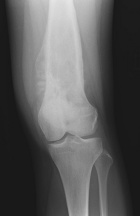

Patient is an 18 y/o female who presented c/o four month hx. of L. knee pain and swelling; she attended PT and x-rays revealed a lesion

PMH: unremarkable; PE: L. distal thigh w/ palpable warm mass; full PROM; NVI

Zoom image: Radiological image Radiological image.